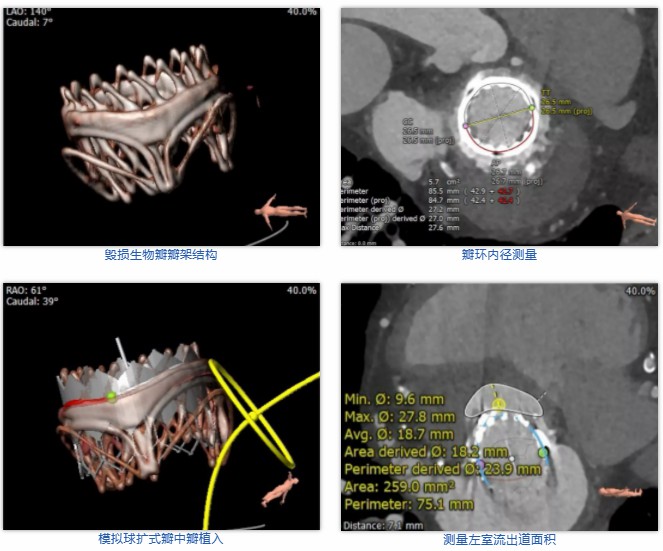

术前经详尽评估患者病情,通过CT重建测量瓣环直径、左室流出道面积。结合之前外科换瓣手术入路,决定采用经心尖途径行二尖瓣“瓣中瓣”手术。术中选用27号Renato®球扩式瓣中瓣,顺利通过心尖途径植入。最终瓣中瓣植入位置理想,功能表现出色,左室造影及经食道超声观察无明显瓣中及瓣周反流。二尖瓣峰值流速由术前3.1m/s降至1.5m/s,平均跨瓣压差由8.3mmHg降至3.6mmHg。

术前经详尽评估患者病情,通过CT重建测量瓣环直径、左室流出道面积。结合之前外科换瓣手术入路,决定采用经心尖途径行二尖瓣“瓣中瓣”手术。术中选用27号Renato®球扩式瓣中瓣,顺利通过心尖途径植入。最终瓣中瓣植入位置理想,功能表现出色,左室造影及经食道超声观察无明显瓣中及瓣周反流。二尖瓣峰值流速由术前2.3m/s降至1.8m/s,平均跨瓣压差由10.8mmHg降至5.9mmHg。